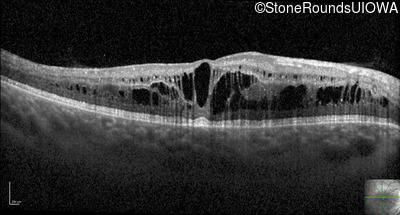

Optical Coherence Tomography - Right - 20/32 -1

Exemplar / OCT Stack

OCT Stack